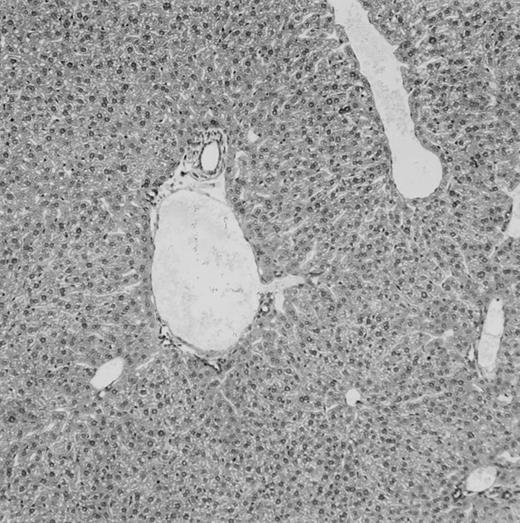

(C) B6 mice receiving FVB BM plus EpΔTK T cells and treated with GCV. (D) B6 mice receiving FVB BM plus EpΔTK T cells, treated with GCV, and developing a late onset GVHD (day 54).

On the other hand, 5 of 19 mice exhibited signs suggesting the occurrence of a delayed GVHD (Table 1). Clinically, these animals presented weight loss and/or skin lesions on ears, neck, limbs, or abdomen, but only after day 40. In the absence of any further GCV treatment, 2 mice died 14 and 29 days after the occurrence of these signs (Table 1A) with histological signs of severe GVHD (Fig 4D). These results suggest that, in these mice, the 7-day GCV treatment was sufficient to prevent early, but not delayed GVHD.